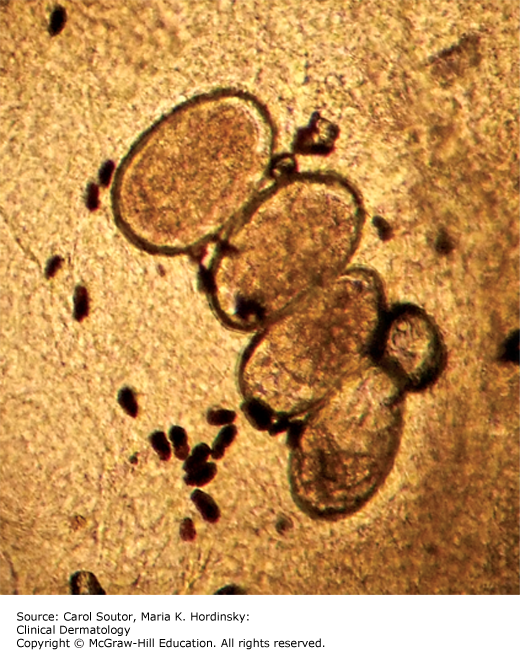

Table 4-3 has instructions for collection and examination of a scabies preparation. The presence of a mite, eggs, or scybala in a scabies preparation confirms the diagnosis (Figures 13-6 and 13-7). Scraping the skin for a scabies specimen is not always easy to do without injuring the patient, particularly if that patient is a squirming child; therefore, other identification techniques have been suggested. Dermoscopy has shown to be a sensitive tool for mite identification.3 Another method is to firmly apply adhesive tape to a burrow, pull it off rapidly and then transfer the tape to a slide for microscopic identification. This has also been shown to be an inexpensive, easy and relatively sensitive way to identify burrow contents.3

Sarcoptes scabiei is an obligate human parasite that completes its entire 30-day life cycle within the epidermis. The fertilized female weaves through the epidermis and leaves a trail of 60 to 90 eggs and feces (scybala), in her burrow (Figure 13-1). The eggs hatch into larvae that then mature into nymphs and adults. The rash and pruritus of scabies is a result of a hypersensitivity reaction to the mite and its detritus. The incubation period from infestation to pruritus can range from days to months. The first time an individual is infested, it typically takes 2 to 6 weeks to become sensitized and develop symptoms, but in subsequent infestations, the previously hypersensitized individual can begin itching in as little as 1 to 3 days. Some infested individuals never develop hypersensitivity to the mite and never experience symptoms, but can still transmit the infection; these are asymptomatic “carriers.”